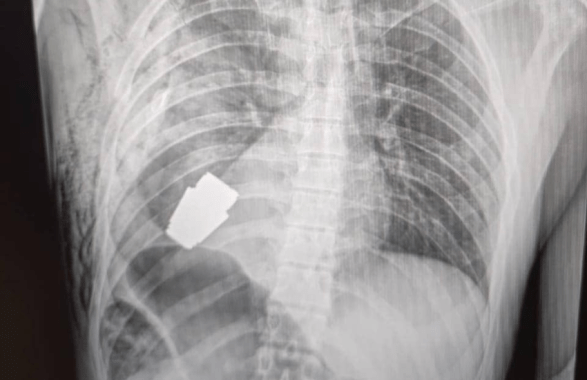

L’esplosivo era rimasto intatto nel torace del soldato, così come mostrano le immagini postate sui social dall’alto funzionario di Kiev: “I medici militari hanno condotto un’operazione per rimuovere una granata VOG, che non si è rotta, dal corpo del soldato”, ha spiegato la Maliar.

La vice ministra ha postato l’immagine di una radiografia in cui si vede l’ordigno all’interno del corpo del soldato e una foto di un chirurgo che osserva la granata dopo l’intervento.

La parte inesplosa della granata si trovava sotto il cuore del militare ferito, ha precisato Gerashchenko.